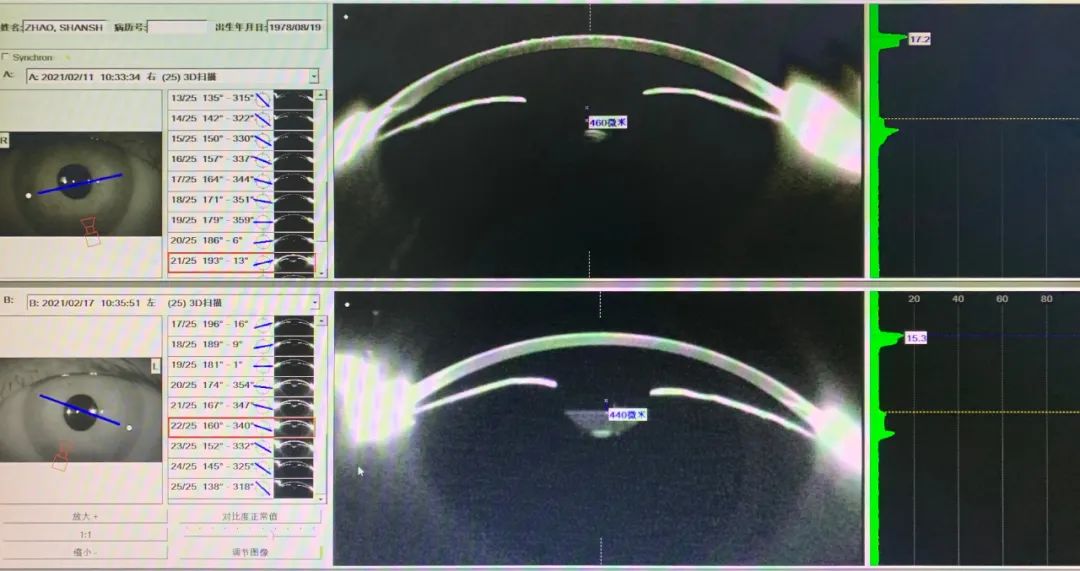

02斜位TICL植入

女42岁,右-8.00D,左-4.50/-1.50x180。右CD11.5 ACD2.80 LT4.45,左CD11.4 ACD2.78 LT4.39。右STS11.32(水平)-11.88(垂直),左STS11.30(水平)-11.94(垂直)。结合前房浅,前房容积小,晶体厚,12.1偏小,12.6略偏大,综合考虑12.6斜放合适。设计右旋转45度,左在DMS库存里找45度左右的现货片,发现一片33度的,最后左定位57度,即水平植入逆时针旋转57度,与45度斜放拱高接近。这样利用库存进行散光片的个性化设计,就实现患者订片零等待。术后拱高右眼460,左眼440。

当然,散光ICL晶体的超常规度数旋转(大于22度)对于手术医生的术前定位标记和术中操作提出了挑战,这些特殊情况仅仅依靠水平标记是不够的,需要术中导航系统的配合与引导。

图4-1

图4-2

图4-3